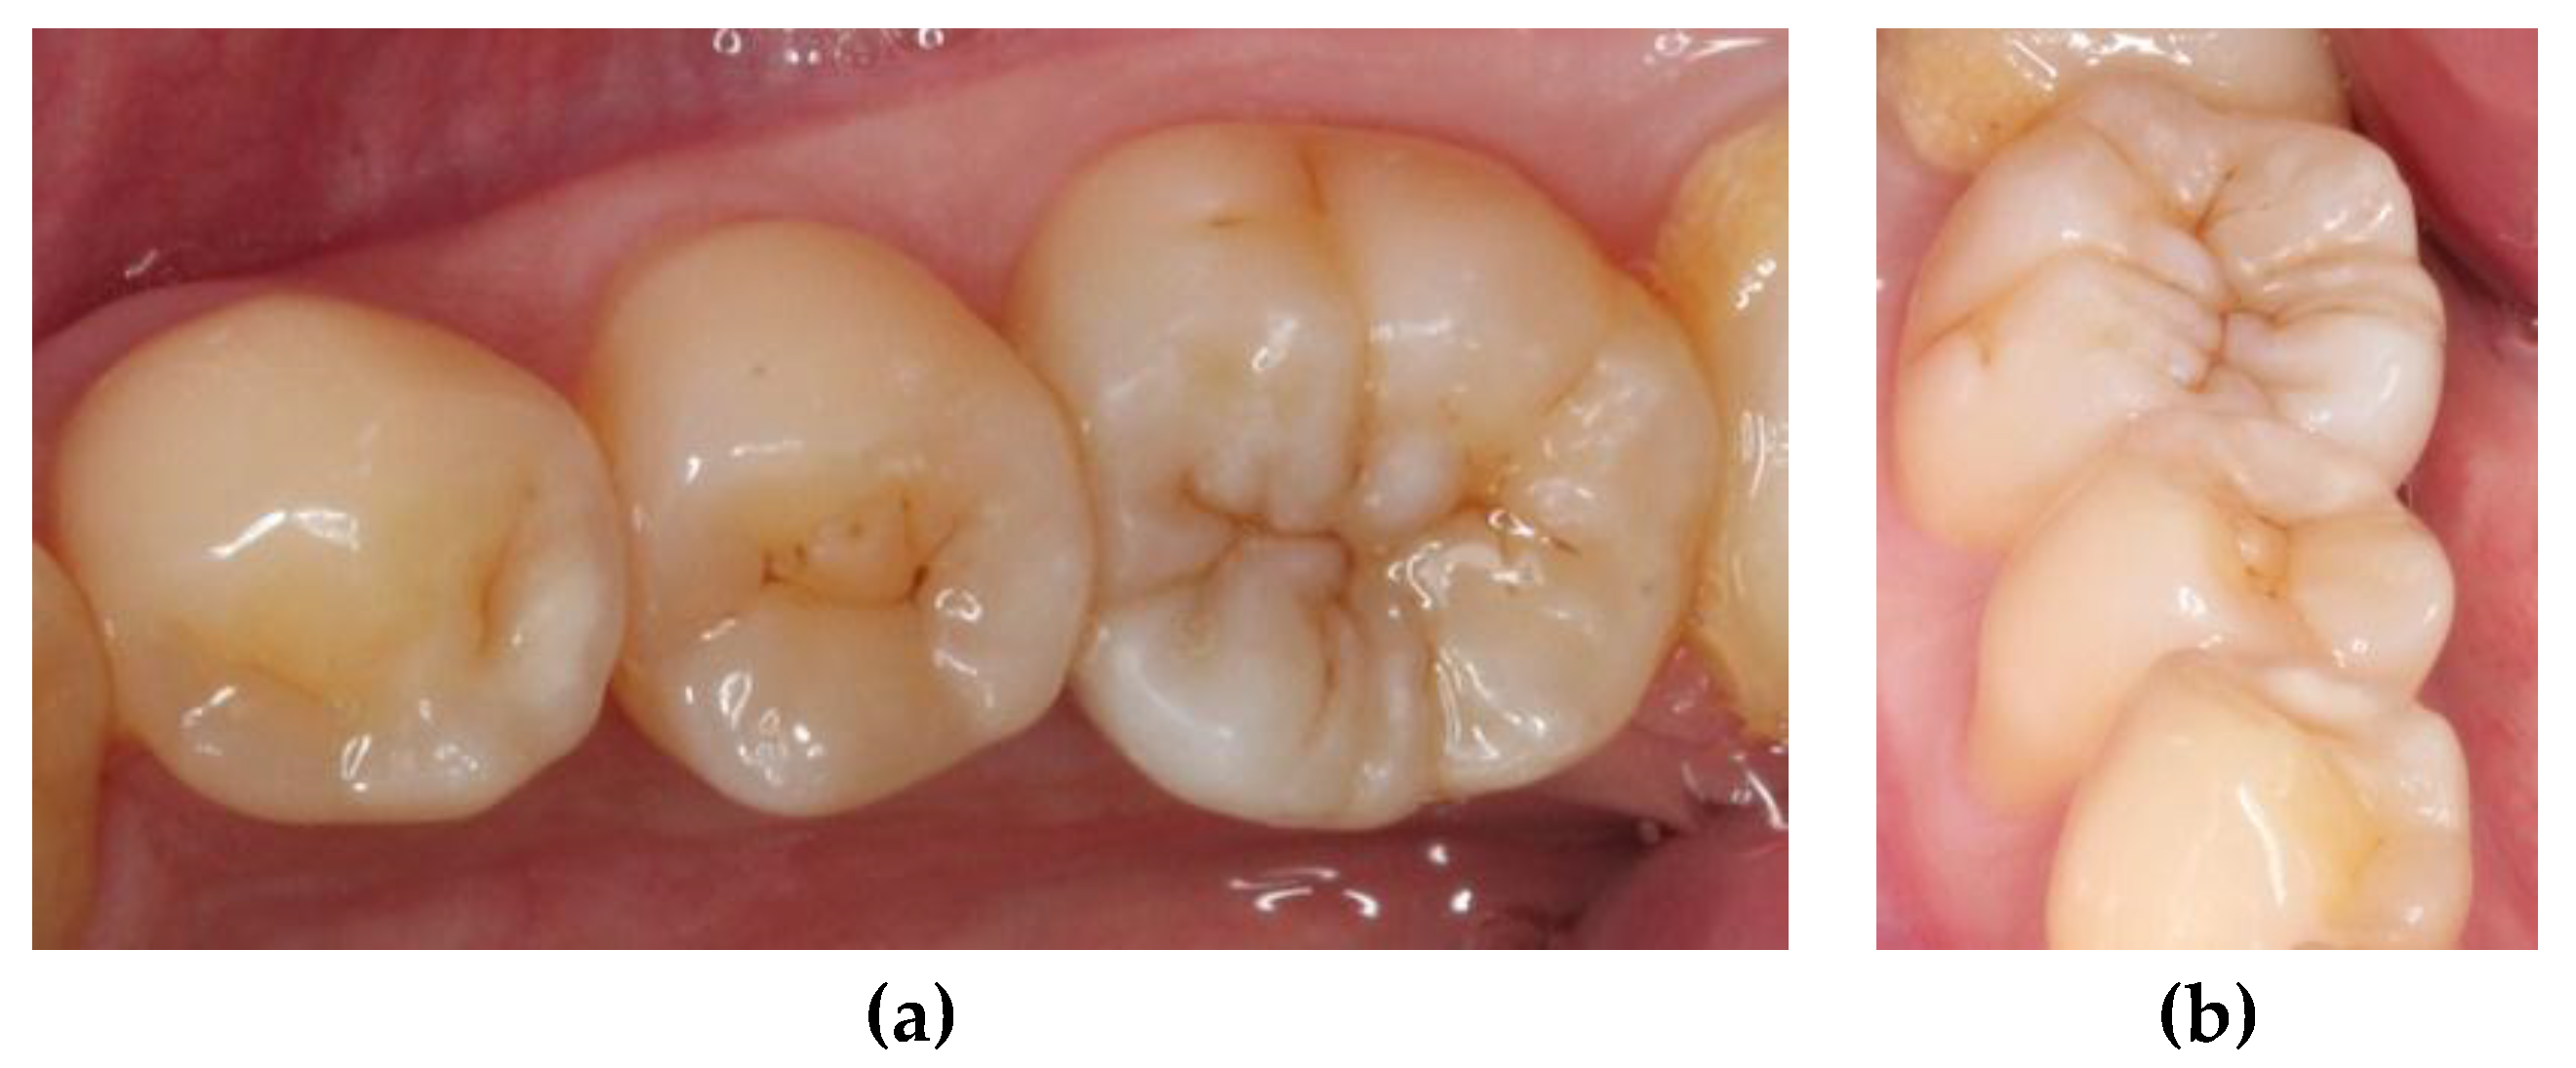

A 22-year-old male student visited the department of restorative and esthetic dentistry of National Taiwan University Hospital for a dislodgement of lower right posterior tooth restoration. He had received direct composite resin filling three years ago, but the old restoration was dislodged while eating popcorn two days earlier. Clinical examination revealed food impaction over the large mesial cavity of the lower right first molar with gingival inflammation (

Figure 1). The pulp vitality test was normal with no symptoms or signs. Radiographic examination revealed a large mesial decay in proximity to the pulp horn while no obvious abnormal apical findings were noted (

Figure 8). At the one-year recall, the restoration still maintained its esthetic and chewing function (

Figure 9).

One of the main purposes of reproducing the natural morphology of posterior tooth is to enhance the mastication function. The restorations must fit into the pre-existing occlusal scheme, where grinding paths are established. This can ensure that iatrogenic interference does not occur because of dental treatment [